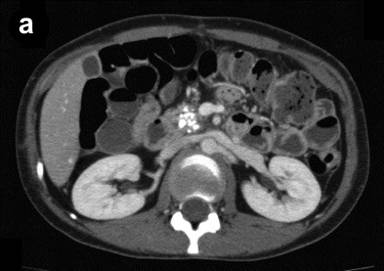

In case #1, the patient was a 38-year-old woman who was diagnosed with alcoholic calcified chronic pancreatitis 8 years ago. She experienced repeated pain episodes which had persisted for the previous three years. The pain was judged untreatable by conservative medical therapy and, therefore, she had undergone a celiac plexus block and pancreaticojejunostomy. Her condition had thereafter improved and she had refrained from drinking for a while. However, she started to experience the pain after resuming drinking two years previously. Abdominal CT revealed a relatively large pancreatic stone in the main pancreatic duct in the pancreatic head (Figure 1a) as well as small diffuse stones in the pancreas (Figure 1b). Although she was advised to stay in the hospital, she refused to be hospitalized because she thought that she would lose her job. Therefore, oral administration of an elemental diet was started at home.

Figure 1. Abdominal enhanced CT in two patients with calcified chronic pancreatitis. a. b. Case #1. c. d. Case #2. |